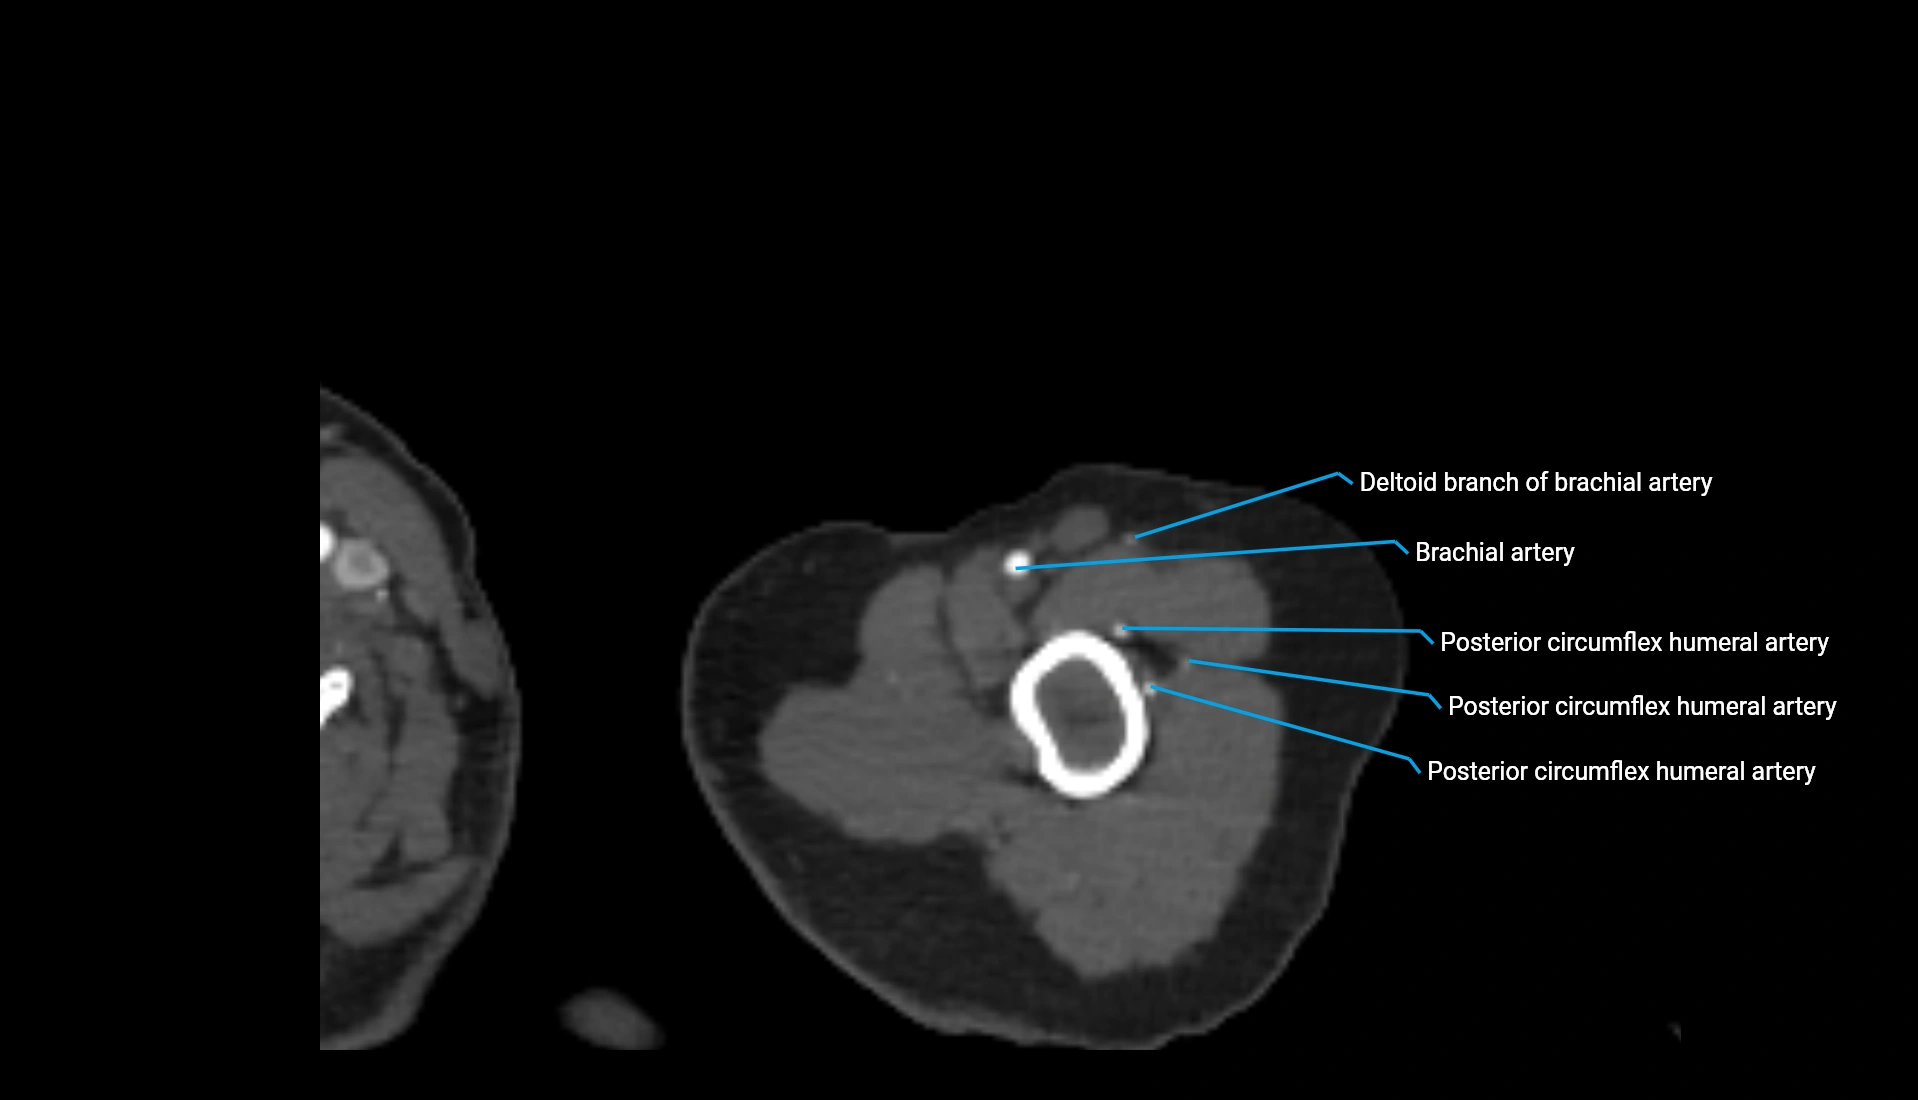

CT Appearance

Non-Contrast CT:

• Cortex: High-density, sharply defined

• Subchondral bone: Dense cancellous matrix

• Articular surface: Smooth concave contour articulating with the capitellum

• Excellent for evaluating bone integrity, alignment, and subtle fractures